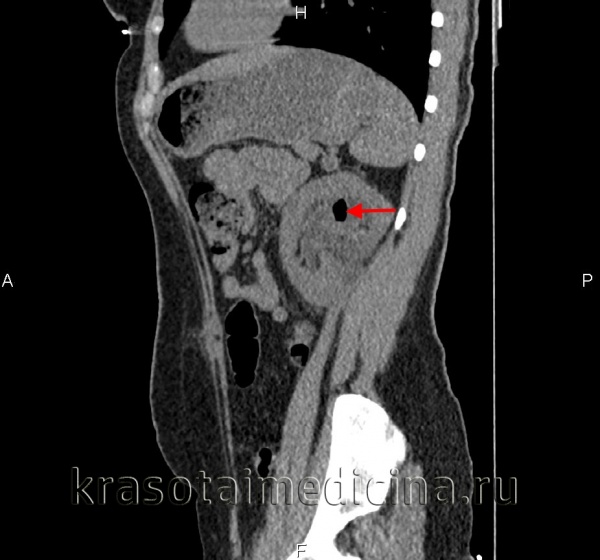

о Клиновидные исчерченные очаги пониженного контрастирования и увеличение размеров почки при контрастной КТ

о Клинообразные или закругленные участки скудного/полосатого окрашивания:

- Лучшая визуализация в нефрографическую и экскреторную фазы

- Мелкие очаги пиелонефрита могут быть пропущены на изображениях в кортико-медуллярную фазу

о Иногда опухолевидные; могут искажать нормальный контур почки